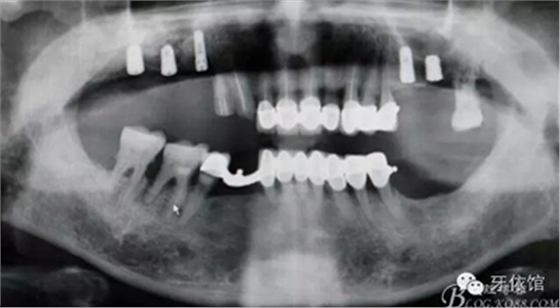

5,6,7擴孔

植入植體同時GBR

縫合

術(shù)后X光片

病例圖片較多,較詳細地闡述了改良式外提升技術(shù)的步驟,自我感覺這種開窗方式更加安全可靠,希望我的這個病例能夠為正在準備做外提升但又不敢貿(mào)然行動的老師們有所幫助。